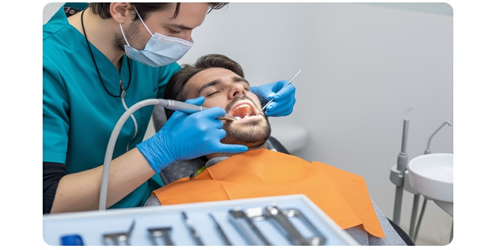

CIRUGÍA

ORAL

Cuidamos de ti y de tu sonrisa con procedimientos

quirúrgicos realizados por especialistas,

comprometidos con tu seguridad, confort

y resultados duraderos.

¿Qué es la Cirugía Oral?

La cirugía oral es la rama de la odontología encargada de diagnosticar y tratar problemas que requieren procedimientos quirúrgicos menores en boca, dientes, encías y maxilares. En LemMor realizamos estos procedimientos con técnicas seguras, mínimamente invasivas y con una recuperación rápida..